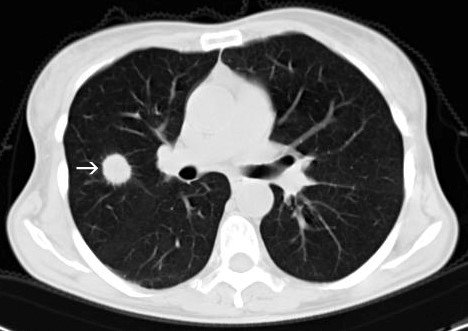

Ağciyərdə tapılan asimptomatik düyündə əsas diaqnostik məsələ törəmənin bəd və ya xoşxassəli olmasını dəqiqləşdirməkdir. Törəmənin bəd xassəli olması inkar edilmirsə çıxarılmalıdır.

- Rentgenoloji müayinədə və ya KT-də ağciyər periferiyasında dairəşəkilli düyün var, digər patologiyalar (plevral maye, limfadenopatiya, atelektaz) yoxdur.

İlk növbədə törəmənin solitar düyün olduğu araşdırlır. Bunun üçün klinik əlamətlər araşdırılır və incə kəsiklərlə (1 mm) KT edilir.

Pulmonar və digər klinik əlamətlər yoxdursa, törəmənin ölçüsü 3 sm-dən kiçikdirsə, parenxima daxilində yerləşmişsə və digər patologiyalar (plevral maye, atelektaz, limfadenopatiya) tapılmırsa solitar ağciyər düyünü kimi qəbul olunur.

İlkin müayinədə təksaylı düyün tapılan xəstələrdə növbəti mərhələdə törəmənin bəd xassəlilik potensialı qiymətləndirilir. Bunun üçün klinik əlamətlər diqqətlə nəzərdən keçirilir, mümkünsə əvvəlki görüntüləmələrlə müqayisə aparılır və KT nəticələri dəyərləndirilir (ölçüsü, kənarlarının quruluşu, kalsifikasiya xüsusiyyəti, əlavə görüntüləmə əlamətləri).

- Bədxassəlilik potensialı yüksək olanlar (65%) – son iki ildə böyümə, kənarları nahamar, kalsifikasiyası yoxdur və ya asimmetrikdir.

- Bədxassəlilik potensialı aşağı olanlar (5%-dən kiçik) – 0.8 sm-dən kiçik, son iki ildə böyüməyib, kalsifikasiyası var (diffuz, hədəf simtpomu, “partlamış qarğıdalı” simptomu, çoxmərtəbəli kalsifikasiya və s.